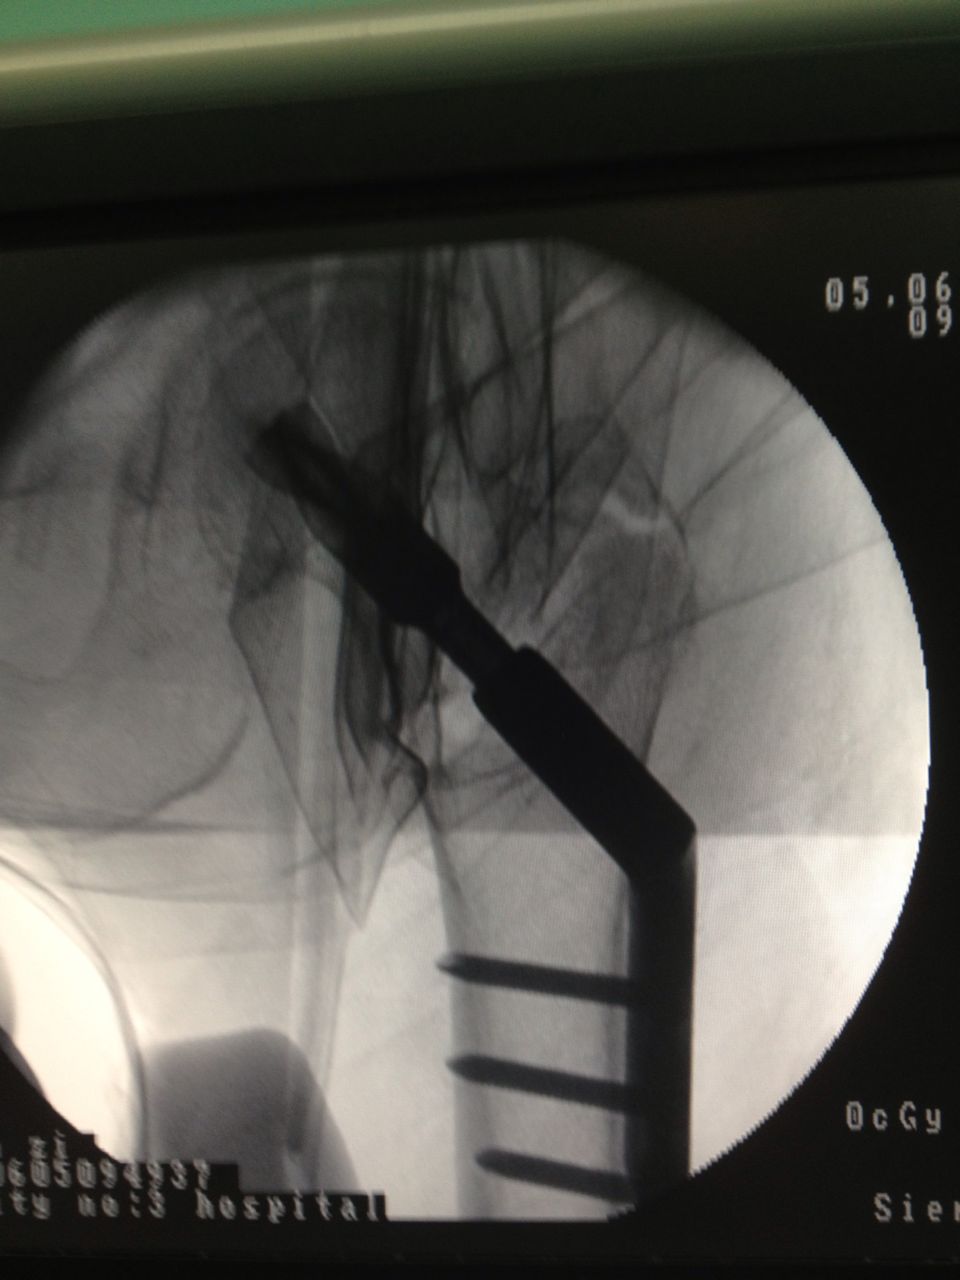

骨科、心内科、麻醉科等多科专家组成的专家组认真仔细分析病情,决定采用髋关节微创植入内固定术。6月4日,老人接受手术,在手术牵引床上,通过C臂X光机透视,不切开骨折端闭合牵引复位,在老人骨折处复位到最佳状态时,刘忠国在骨折处开出5公分的口进行螺旋刀片动力髋固定,最大程度减少手术损伤,促进骨折端提早愈合。

手术很成功,老人术后6-8小时就能坐起,第二天已能下床略走几步。恢复行走的林老太竖起大拇指,直夸三院骨科医生技术高超。